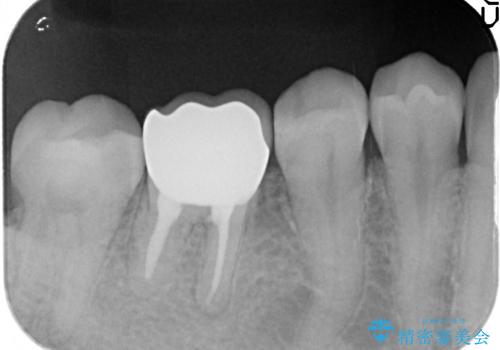

検査の結果右下6に根尖病変を認めたため、再根管治療を行いました。

その後症状の消失を確認し、オールセラミッククラウンによる補綴を行いました。

今回用いたオールセラミッククラウンはジルコニアフレームという白い素材の上にセラミックを盛っているため、審美性が非常に高いのが特徴です。

また、ジルコニアは人工ダイヤモンドの材料にも使われているほど高い強度を持っており、そのためオールセラミッククラウンは審美性だけでなく、奥歯やブリッジの補綴も可能とするクラウンです。